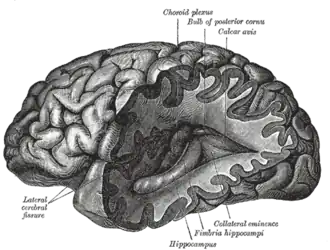

Physiology

The most pronounced physiological changes in sleep occur in the brain.[12] The brain uses significantly less energy during sleep than it does when awake, especially during non-REM sleep. In areas with reduced activity, the brain restores its supply of adenosine triphosphate (ATP), the molecule used for short-term storage and transport of energy.[13] In quiet waking, the brain is responsible for 20% of the body's energy use, thus this reduction has a noticeable effect on overall energy consumption.[14]

Key physiological methods for monitoring and measuring changes during sleep include electroencephalography (EEG) of brain waves, electrooculography (EOG) of eye movements, and electromyography (EMG) of skeletal muscle activity. Simultaneous collection of these measurements is called polysomnography, and can be performed in a specialized sleep laboratory.[16][17] Sleep researchers also use simplified electrocardiography (EKG) for cardiac activity and actigraphy for motor movements.[17]

Brain waves in sleep

The electrical activity seen on an EEG represents brain waves. The amplitude of EEG waves at a particular frequency corresponds to various points in the sleep-wake cycle, such as being asleep, being awake, or falling asleep.[18] Alpha, beta, theta, gamma, and delta waves are all seen in the different stages of sleep. Each waveform maintains a different frequency and amplitude. Alpha waves are seen when a person is in a resting state, but is still fully conscious. Their eyes may be closed and all of their body is resting and relatively still, where the body is starting to slow down. Beta waves take over alpha waves when a person is at attention, as they might be completing a task or concentrating on something. Beta waves consist of the highest of frequencies and the lowest of amplitude, and occur when a person is fully alert. Gamma waves are seen when a person is highly focused on a task or using all their concentration. Theta waves occur during the period of a person being awake, and they continue to transition into Stage 1 of sleep and in stage 2. Delta waves are seen in stages 3 and 4 of sleep when a person is in their deepest of sleep.[19]